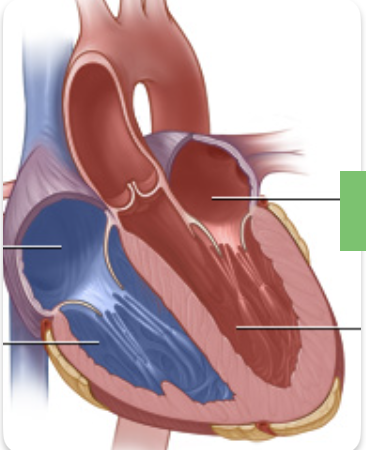

pink

interatrial septum

dark blue

interventricular septum

aortic valve

yellow

pulmonary valve

red

tricuspid valve (right AV)

purple

bicuspid valve (left AV)

yellow

chordae tendineae

orange

papillary m.

blue

trabeculae carneae - only in ventricles

red

pectinate m. - only in R atrium

pink

fossa ovalis

grey

opening of coronary sinus

green

fibrous pericardium

blue

parietal pericardium

pink

visceral pericardium (connective tissue) / epicardium (muscle)

purple

myocardium

grey

endocardium